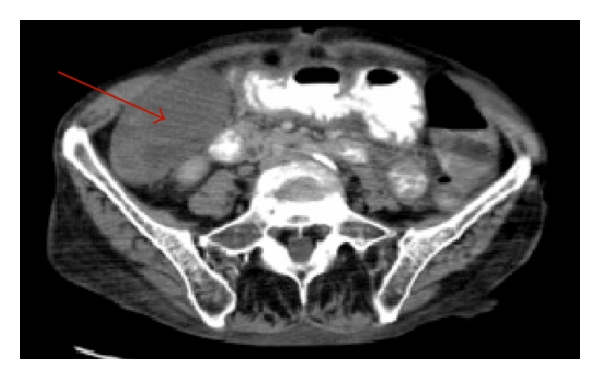

The patient was evaluated by surgery on hospital admission day #10. By the time surgery evaluated the patient, she had four bowel movements, one of which was loose in nature, and she stated her abdominal pain was much improved. Physical exam did reveal abdominal pain with light or deep palpation in the right lower quadrant, directly over McBurney’s point. An abdominal X-ray was obtained which was unremarkable and new labs were sent at this time. The complete blood count (CBC) did show an acute elevation of the WBC to 16.4 K/μL. Because of this acute elevation in WBC and concern for appendicitis on physical exam, we ordered a computed tomography (CT) scan of the abdomen and pelvis. The CT scan demonstrated an 8.2 cm × 4.8 cm heterogeneous “fluid collection” within the right lower quadrant. An abscess could not be ruled out from the imaging nor could acute cholecystitis. The appendix did appear normal however. Figures 1 and 2 demonstrate the identified fluid collection on CT scan.